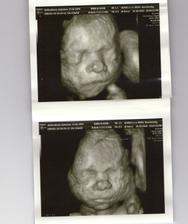

3D - nas poklad

Nas drobcek na 3D

bolo to teraz v nedelu 24.10 a bola som 22 tyzden 5 den.Ale mala je o tyzden popredu tak podla merania lekara bola 23 tyzden 5 den